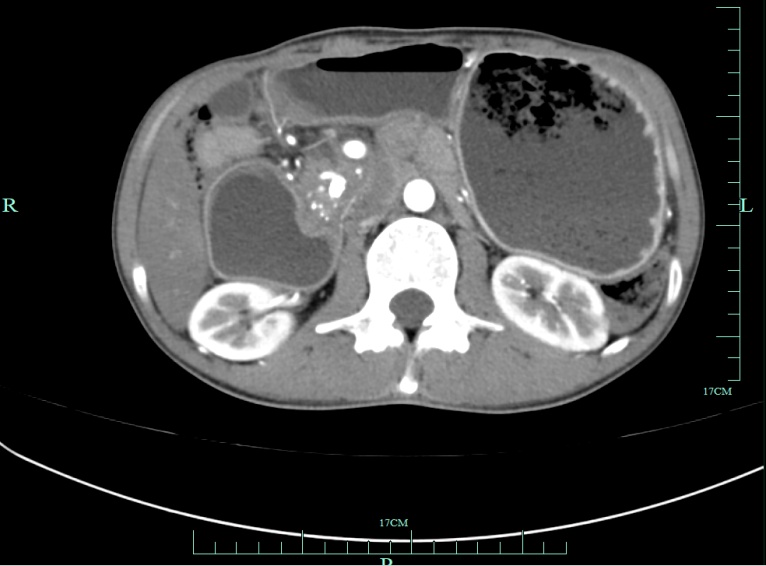

赵磊的腹部CT显示胰头异常

考虑肿瘤病变的可能